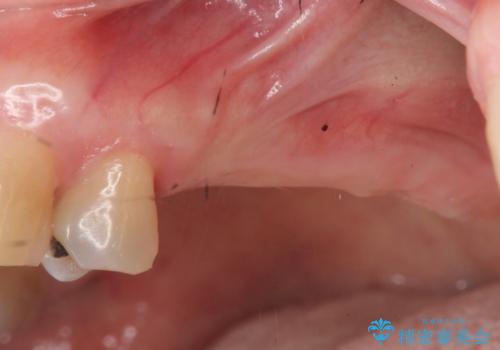

- 奥歯に入れていたブリッジがダメになり歯を抜去、全然噛めなくなった、インプラント治療を受けたい!と奥歯の機能回復を希望され来院されました。

奥歯はすでに3本失った状態で、この状態で歯を入れるには「入れ歯」か、「インプラント」の2択となります。